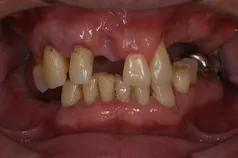

[症例1]

重度の歯周病で奥歯がすでになくなっており、そのため前歯もグラグラの状態でした。

右上の前歯(向かって左上)は自然に抜け落ちたそうです。

下の前歯の裏側には多量の歯石がたまっています。

【処置内容】

歯周初期治療、全体に歯周外科処置を実施、その後セラミックブリッジ、セラミッククラウン、

右上6・5番、左上3・4・5・6番、左下6番、右下4・6番にインプラントを実施。

• 治療期間:約2年

• 治療費:400万円

• 治療回数:30回